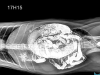

X-quang răng thú cưng là kỹ thuật chẩn đoán hình ảnh sử dụng tia X để kiểm tra răng, nướu, xương hàm và cấu trúc răng sâu bên trong của chó, mèo. Đây là phương pháp quan trọng giúp bác sĩ phát hiện các vấn đề răng miệng mà mắt thường khó nhận thấy.

Tại Bệnh viện Thú Y Sing Pet Đồng Nai, dịch vụ X-Quang Răng Thú Cưng Biên Hòa sử dụng máy X-quang kỹ thuật số hiện đại, cho hình ảnh rõ nét, hỗ trợ chẩn đoán chính xác các bệnh lý nha khoa và chấn thương răng.

Hiển thị toàn bộ cấu trúc răng, xương hàm và khớp cắn, phát hiện các tổn thương sâu bên trong.

• Trang thiết bị hiện đại: máy X-quang kỹ thuật số giúp hình ảnh sắc nét, dễ dàng đánh giá.